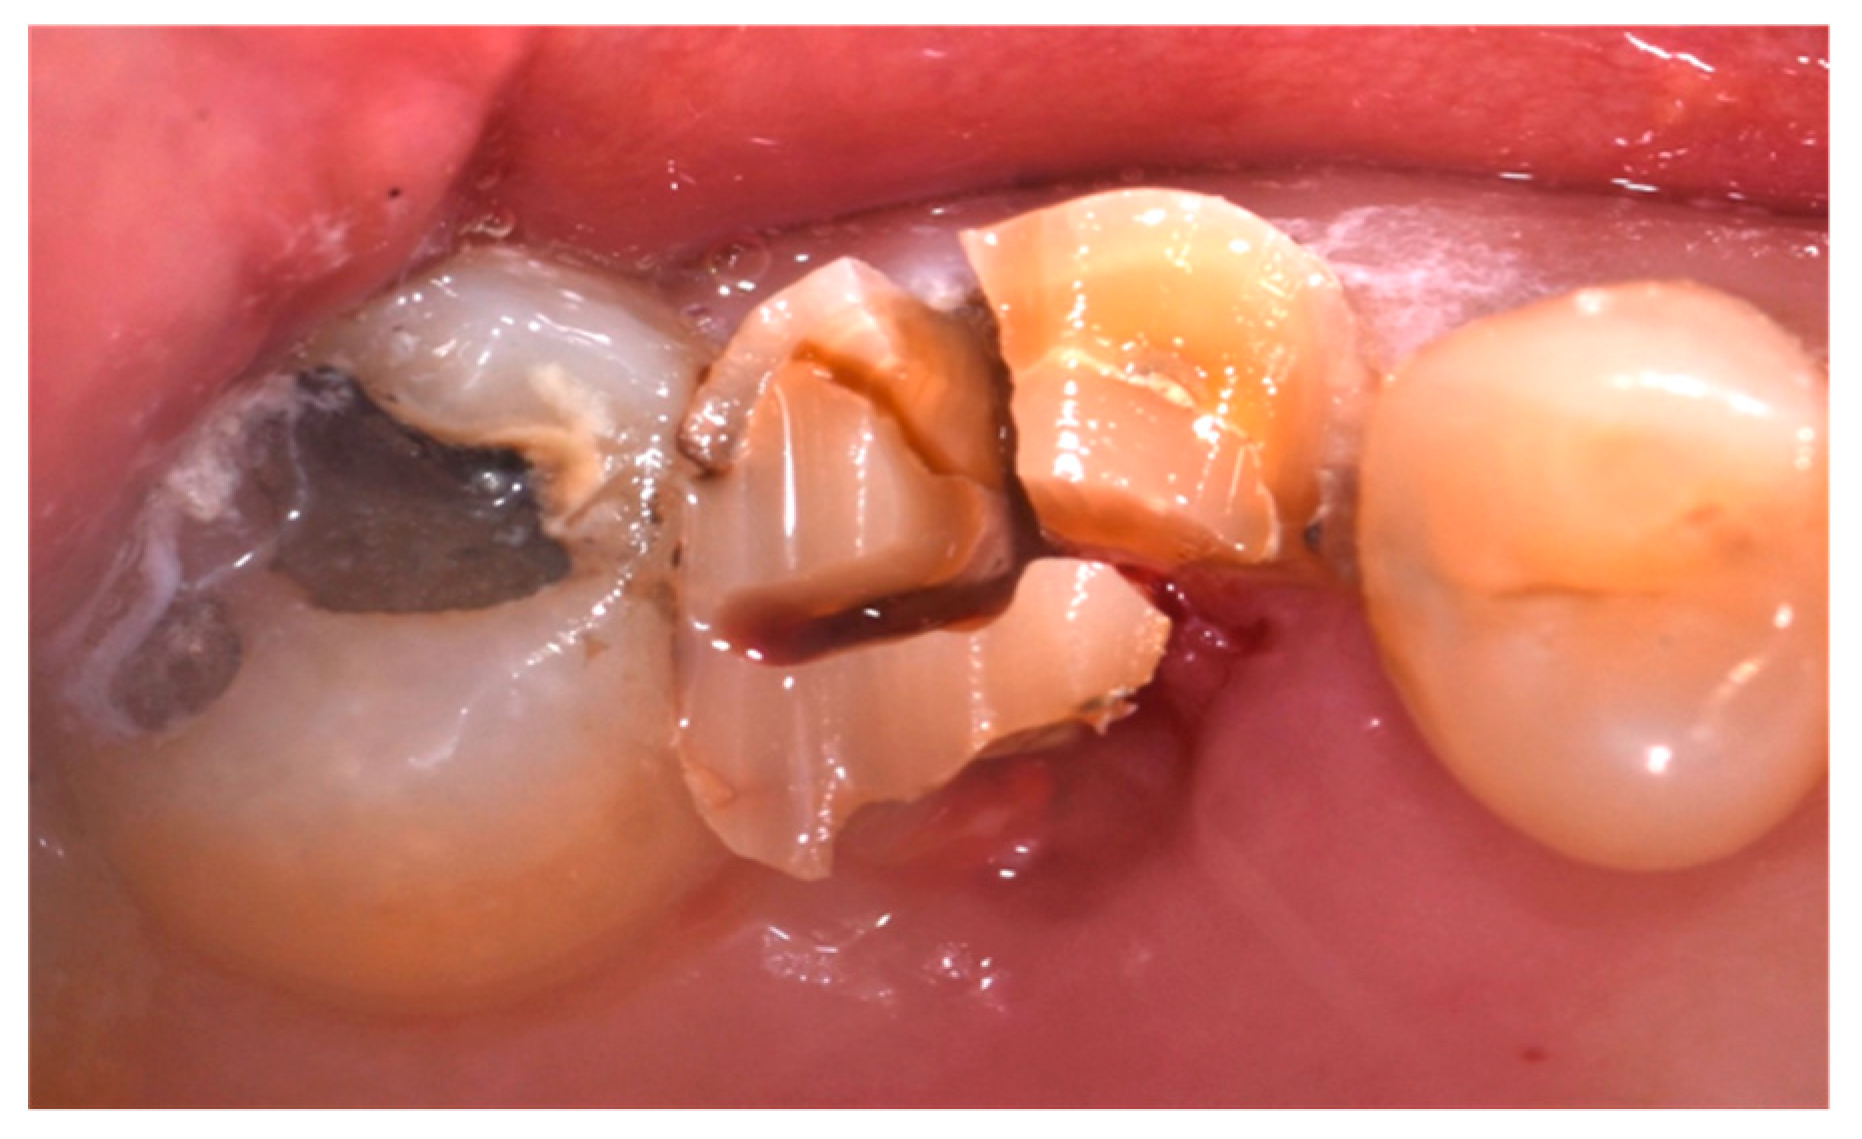

- Cause of extraction: caries, orthodontic reasons, or trauma;

2.4. Surgical Procedure, Evaluation at Follow-Up, and Collection of Radiographic Data